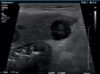

What is shown in these images?

A

ultrasound of the gall bladder:

-top: anechoic bile

-bottom: sludge (normal in dogs)